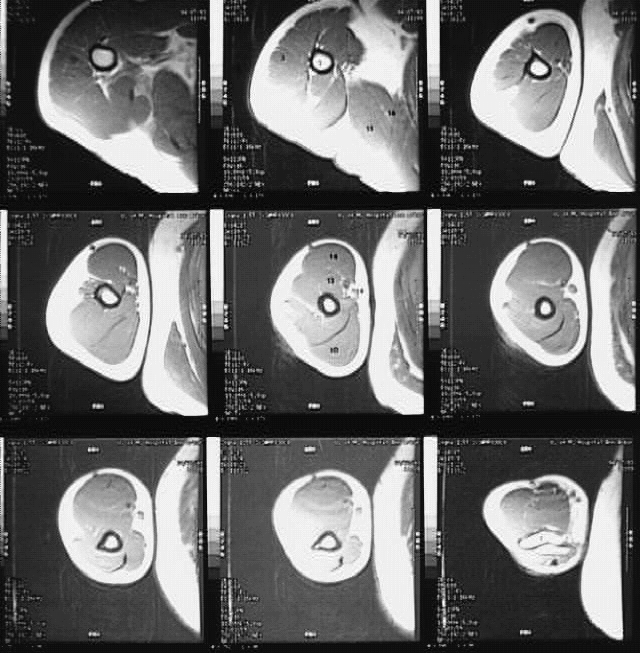

Radiology Images

Upper Limbs: Arm MRI Cross: